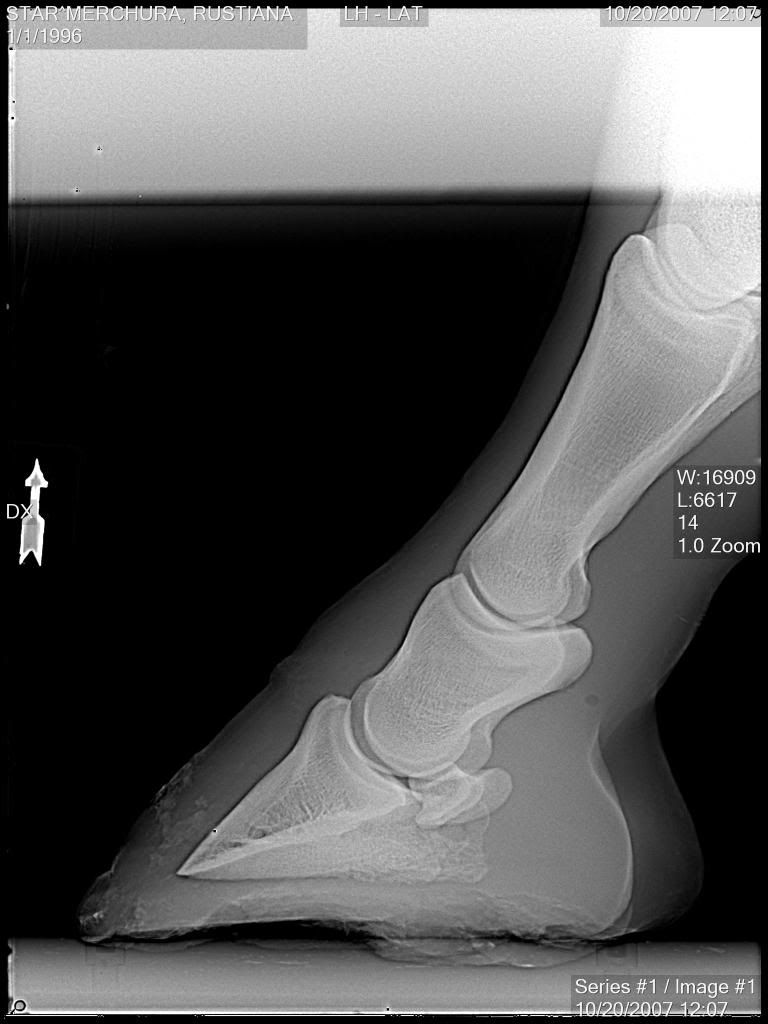

From www.theequinedocumentalist.com

WetDry Cycles Effect on the Hoof Horse Hoof Sloughing Off if a horse's hoof begins to detach or slough off, it is crucial to seek immediate veterinary care. The outer part of the horse’s hoof is known as the hoof wall. This is a hard keratin surface that’s consistently growing, and it grows from the coronet. the pics didn't turn out that great, but it kind of looks. Horse Hoof Sloughing Off.